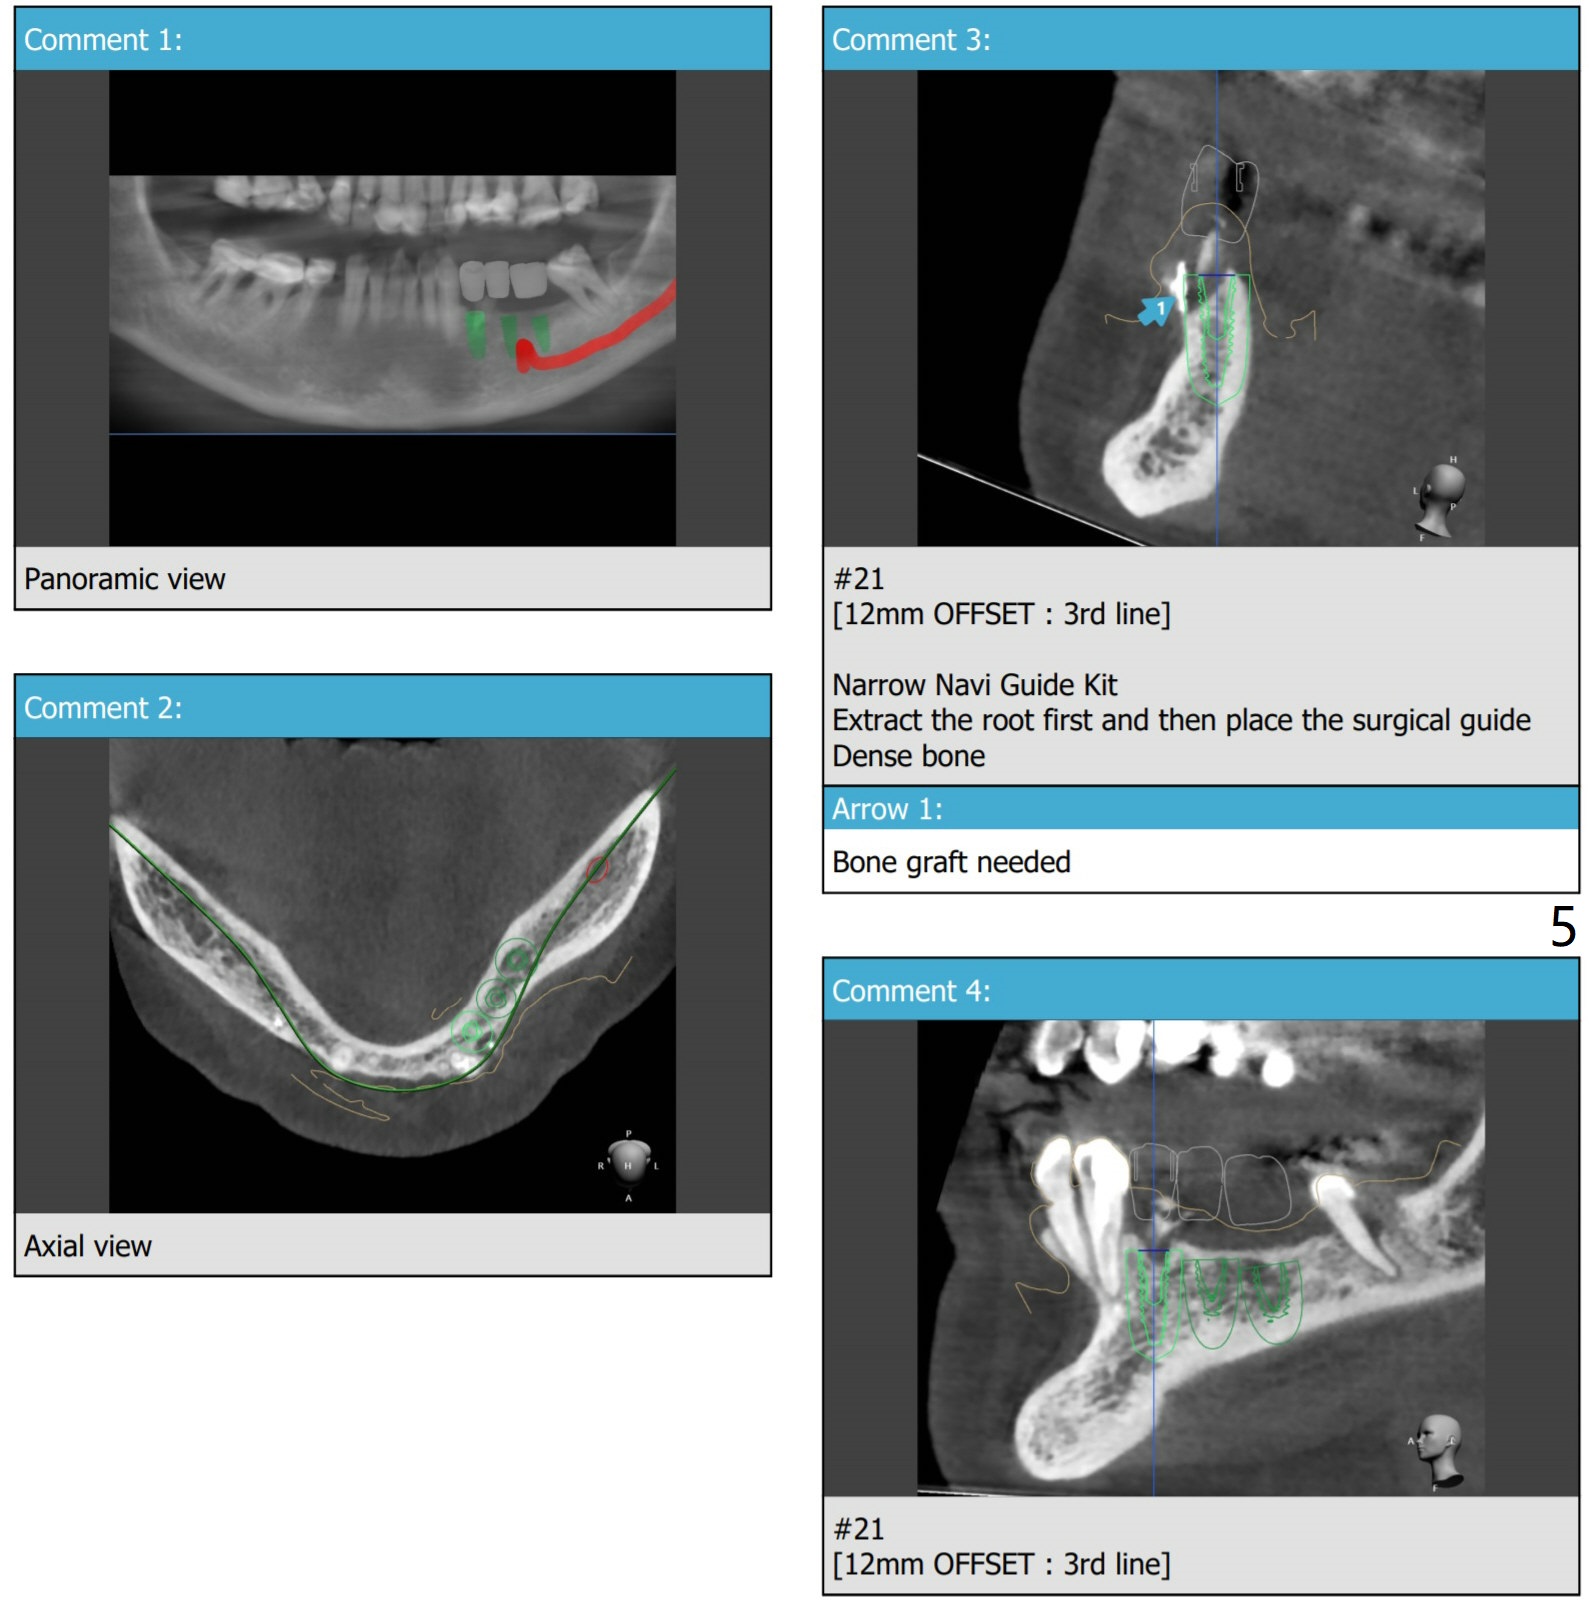

3 Implants In a Row

Yes you can but, I think you'll be able to connect fixture mount on #20 only because there's only one you can use in the narrow naviguide kit.